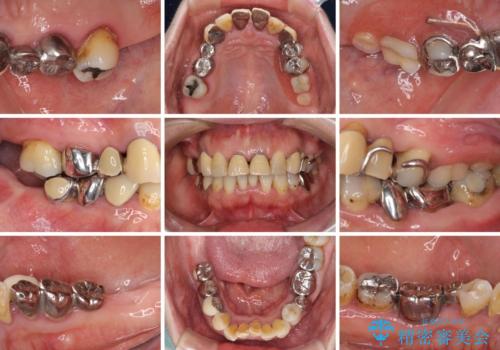

- 歯茎からの出血、入れ歯、歯の欠損、デコボコの前歯などを気にして来院された患者様です。

大の歯科治療嫌いとのことでしたが、今回の治療を契機にしっかりと治療を行いたいとのことでした。

まずは抜歯が必要な歯を抜歯した上で仮歯に置き換え、インプラント埋入や歯周外科処置、根管治療を行うこととしました。